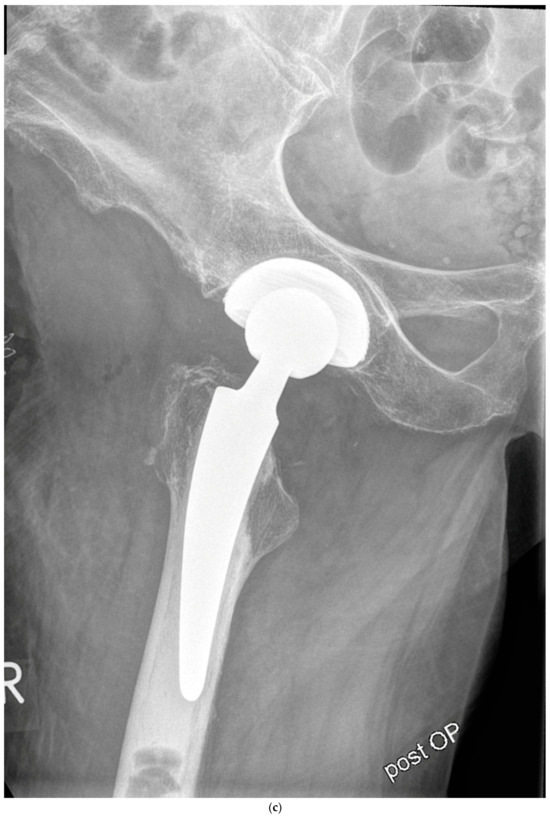

Case #1: Female patient, 81 years old, with osteoporotic bone, coxa vara, and a Dorr C femur. (a) Preoperative planning for a cemented A2 stem combined with a cementless ANA.NOVA Alpha Cup. The image shows good reconstruction of the leg length and offset. (b,c) Postoperative anteroposterior (b) and axial (c) radiographic imaging 1 week postoperatively. Correct position of the stem and complete cement mantle.